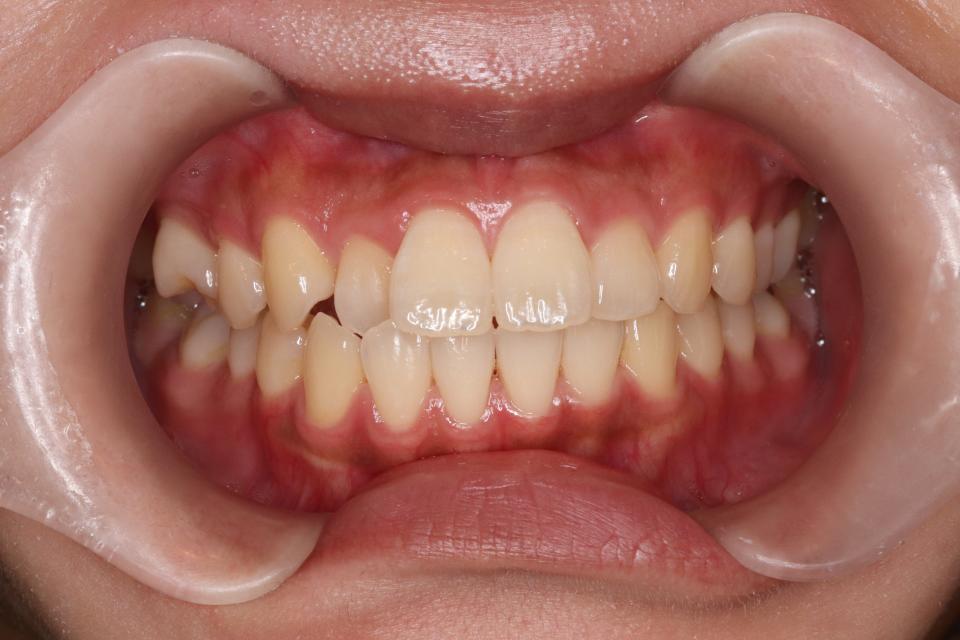

矯正治療前

前歯が出ているのと隙間が気になる、と当院に来院されました。